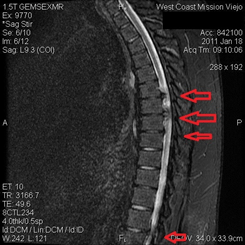

T5-T6: 4 mm disc protrusion

T6-T7: 10-11 mm disc protrusion

T7-T8: 9 mm disc protrusion

T8-T9: 3-4 mm disc protrusion